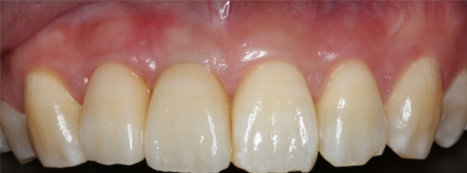

前歯が割れてしまってインプラントをご希望で来院された患者様です。

前歯に亀裂が入ってしまっており、抜歯後、インプラント治療を行いました。

非常に審美的な治療が出来ました。

当院では難しい前歯のインプラントも違和感なくきれいに処置することが出来ます。